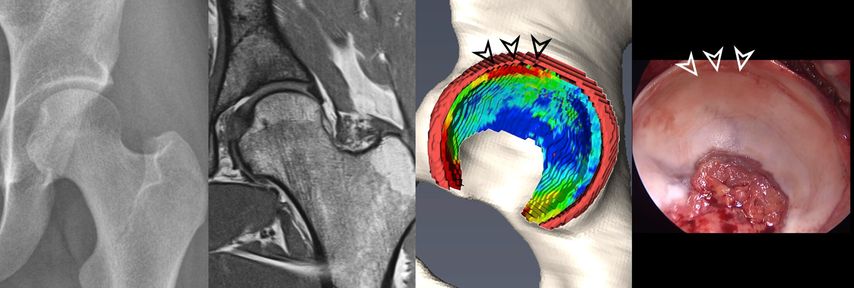

Fig. 2: 3D models of hip cartilage and labrum with color-coded dGEMRIC indices to visualize biochemical cartilage degeneration (red color, black arrowheads) which was confirmed during surgery (white arrowheads).

More recently, we introduced a deep-learning-based approach for automatic segmentation of hip cartilage and labrum using a 3D dGEMRIC sequence (MP2RAGE). The approach allows for automatic and reliable generation of 3D models of hip cartilage and labrum within seconds, and providing both 3D morphologic information of the hip joint as well as color-coded dGEMRIC indices for quantitative analysis of cartilage damage (Fig. 2 & 3).19

Fig. 3: Two patients with cam deformity of the proximal femur. Pelvic X-ray shows in both cases only mild arthritic changes. The morphologic MRI only allows 2D morphologic assessment of damage. The 3D cartilage models allow for a quantitative and 3D assessment of cartilage degeneration. Compared to the patient with good cartilage quality (blue color coding) who underwent impingement surgery the patient below showed too advanced signs of cartilage damage (red color coding) and thus underwent total hip replacement.